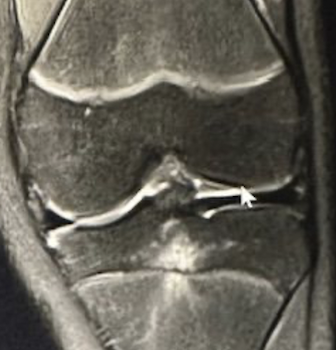

- This one-hour postgraduate lecture provides a focused, clinically practical approach to the evaluation of knee pain and dysfunction. Emphasis is placed on functional anatomy, MRI anatomy, common mechanisms of injury, and appropriate imaging utilization in acute trauma and chronic knee conditions. Participants will integrate orthopedic examination findings with imaging interpretation and instructive case reports to improve diagnostic accuracy, recognize not-to-miss pathology, and guide appropriate conservative care or referral.

- MRI anatomy and common imaging pitfalls

- Describe knee anatomy and MRI findings relevant to common and serious knee disorders.